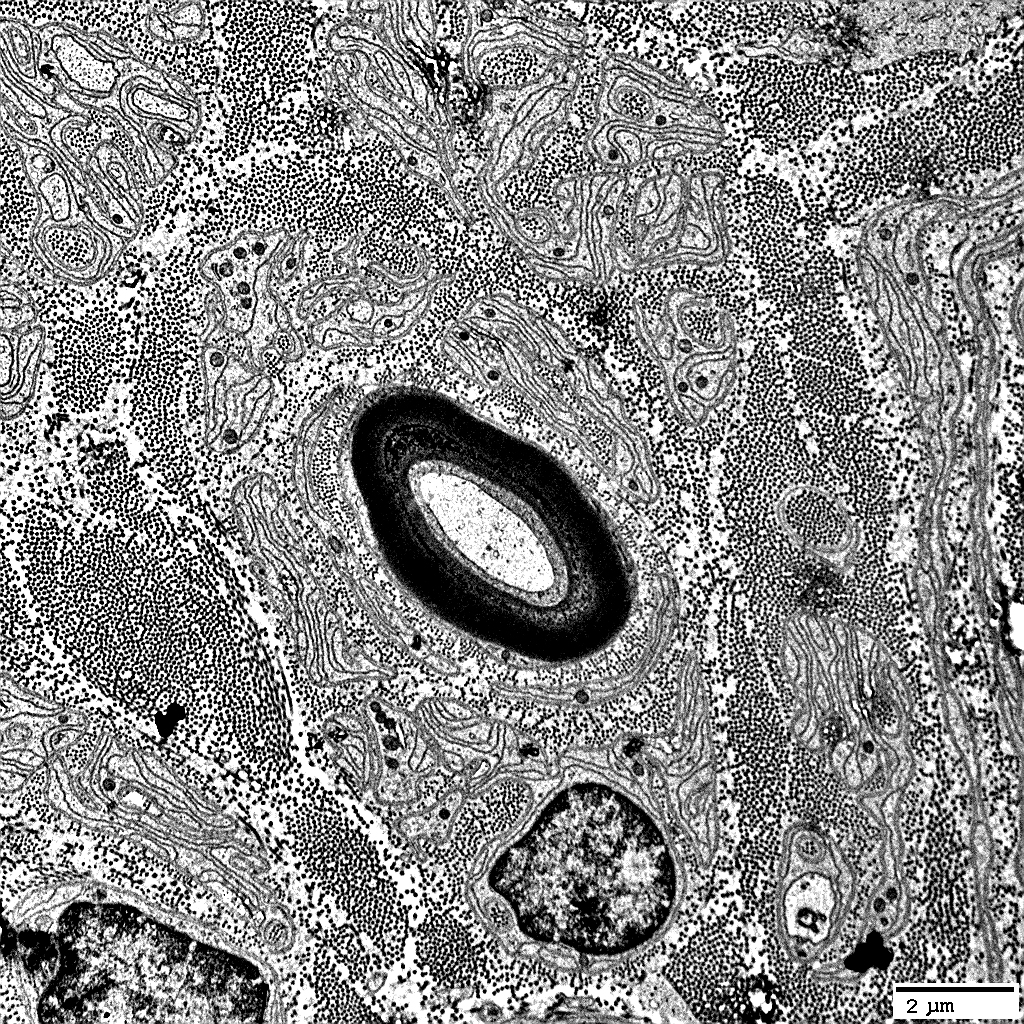

Schwann cells in Onion bulbs

Contain:

NCAM &

P0 protein

Non-myelinating Schwann cells in onion bulbs: In layers

Myelin around central axons: Abnormal; Stains for NCAM